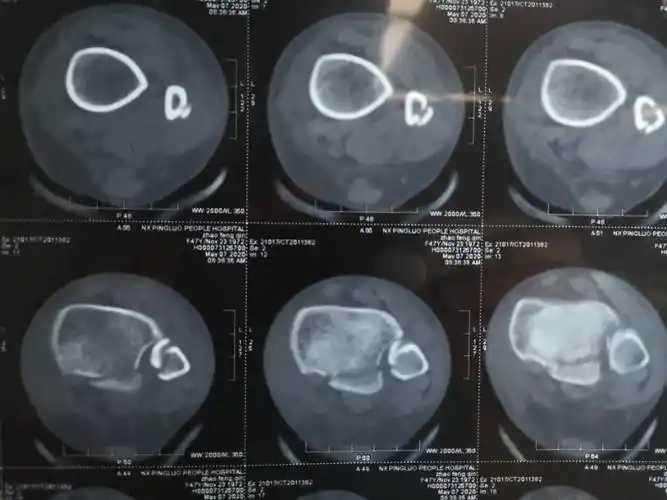

踝关节横断面ct